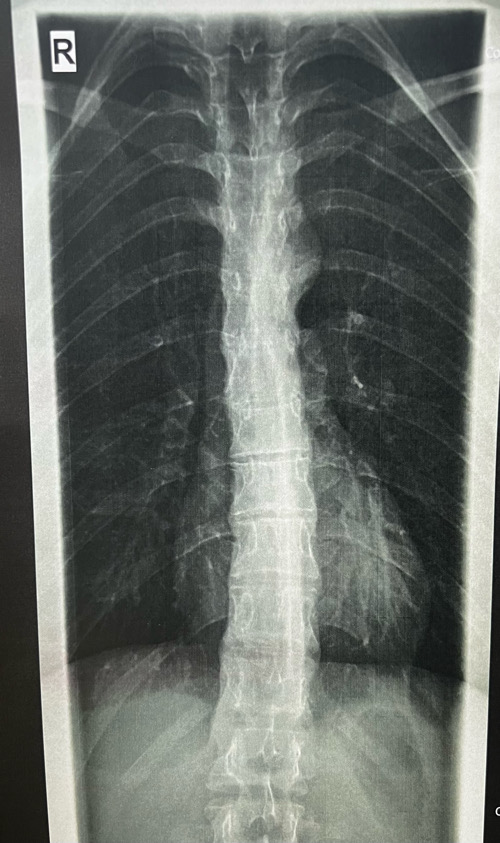

heute war ich nochmal bei meinem Orthopäden und habe die Röntgenbilder abgeholt. Ich wollte wissen, wo und ob ich wirbelveränderungen habe, weil der Orthopäde sich nicht wirklich bei meinem Termin dazu geäußert hat. Leider konnte mir bei der Rezeption niemand helfen und es wurde nur gesagt, wahrscheinlich leicht.

Ich dachte ich stelle hier nun mal die Bilder ein. Einmal von der Seite und von vorne. Der Bericht mit der Diagnose ist auch dabei. Kann jemand anhand der Röntgenbilder offensichtliche Keilwirbel erkennen und vielleicht auch grob was zu dem Kyphosewinkel sagen. Ich selber glaube Ansätze von keilwirlbel zu sehen, aber ich bin mir nicht sicher.

Musste die Aufnahmen von der Qualität etwas verkleinern, da ich sie sonst nicht hätte einfügen können.

Die Messung vom BWS Kyphosewinkel erfolgt mittels der sogenannten Neutralwinkel, das sind die Wirbel am Wendepunkt zur HWS Lordose und der LWS Lordose. Der HWS Übergang ist schwer zu sehen und der LWS Übergang kaum sichtbar, weil es nur eine BWS Aufnahme ist.

Deshalb sollte immer eine Röntgen-Ganz-Aufnahme (LWS, BWS und HWS) gemacht werden. Frau Dr. von Ricthofen kann solche Aufnahmen machen. Grob kann ich nur sagen, dass die in der Diagnose erwähnte "vermehrte Kyphosierung" bzw. später im Text "leicht vermehrte Kyphosierung" nachzuvollziehen ist.

Es sieht für mich aber so aus, als ob der obere Kyphosebogen zu flach ausgeprägt ist.

Also grundsätzlich finde ich die Beantwortung dieser Fragen problematisch, weil das den Ärzten bzw. den Spezialisten vorbehalten ist und Dich aktuell auch gar nicht weiterbringen würde.Kann jemand anhand der Röntgenbilder offensichtliche Keilwirbel erkennen und vielleicht auch grob was zu dem Kyphosewinkel sagen

Zu Keilwirbel kann ich nur sagen, dass die in der Regel an der Behandlung nichts ändern. Es kann je nach Anzahl und Lage dieser Wirbel u.U. die Behandlung mehr oder weniger beeinflussen.

Ich habe mir deine Bilder angeschaut. Da ich selber zig Bilder analysiert und mit Software ausgemessen hab, kann ich dir folgendes mitteilen:

- Der globale Cobb-Winkel, definiert als der Winkel zwischen dem meist geneigten BWS-Wirbel im unteren Segment (das ist häufig T11 oder T12) und dem meist in-die-andere-Richtung-geneigten BWS-Wirbel im oberen Segment (T1 bis T4 häufig) kommt bei dir auf ca. 55 Grad zu belaufen.

- Manchmal wird auch implizit der Stagnara-Winkel gemessen, und als Cobb-Winkel ausgewiesen. Dieser ist strikte definiert als der Winkel zwischen T4 und T12 und wird häufig angewendet, weil die oberen Wirbel (T1 bis T3) auf dem Bild nicht klar ersichtlich sind. Da ich nicht genau identifizieren kann, welcher Wirbel welcher ist, kann ich es nicht genau sagen, ich schätze aber auch hier, dass 42 Grad zu tief bemessen ist.

- Viele deiner BWS-Wirbel sind milde verkeilt (zwischen 5 und 10 Grad). Man spricht von Keilwirbel ab 5 Grad. Das ist nicht sonderlich viel und wird leider von vielen Docs/Spezialisten komplett übersehen. Wenn mehrere Wirbel betroffen sind, führt das aber sehr schnell zu einer strukturellen Verkrümmung, genau so wie in deinem Fall.

- Die einzige Bedingung, die für eine Diagnose des klassischen Morbus Scheuermann erfüllt sein muss, ist, dass drei oder mehr aufeinander folgende BWS-Wirbel eine Keilform von 5 Grad oder mehr haben. Daneben gibt es eine Reihe von radiologischen Eigenschaften, welche alle auf einen Morbus Scheuermann hinweisen bzw. gehäuft mit diesem in Erscheinung treten, nicht aber notwendig für die Diagnose sind: Schmorl-Knoten, Grund- und Deckplatten-Unregelmässigkeiten, verschmälerte Zwischenwirbelräume, globaler Cobb-Winkel von mehr als 40/50 Grad (je nach Quelle und Messmethode).

- Der Cobb-Winkel ist aus diversen Gründen mit Vorsicht zu interpretieren: Es wird keine Unterscheidung zwischen struktureller Verkeilung von Wirbelkörpern und Bandscheiben (z.B. weil sie asymmetrisch degeneriert sind) und der physiologischen Verkeilung/Verformung von Bandscheiben bei z.B. einer Haltungsschwäche gemacht. Es wird einfach alles addiert. Es versteht sich von selbst dass der Grad der Unsicherheit hier enorm sein kann. Darum ist vor allem der Grad der individuellen Verkeilung der Wirbelkörper entscheidend. Ein MRI gibt zudem Aufschluss über den Zustand der Bandscheiben, und ob es bereits zu einer frühen Degeneration gekommen ist.